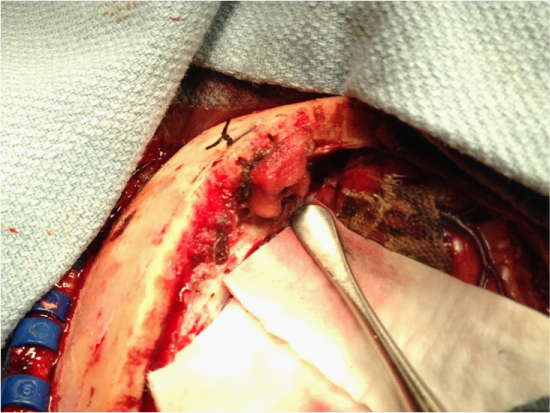

As we were scrapping the tumor capsule from the lateral wall of the SSS, a laceration of the sinus had occurred in the anterior portion of the sinus. The bleeding site was controlled with multiple layers of Surgicel (Ethicon), Gelfoam (Pfizer) and cottonoids. The site of bleeding remained under control while we maintained pressure at the lacerated area. However, despite adequate packing the site would continue to bleed when manual pressure was removed. It was not prudent for us to do a primary closure due to the limited craniotomy exposure near the sinus. At this point, instead of extending the craniotomy, we planned to apply a tension suture over the lacerated site assisted by the adjacent falx cerebri. The bony edge was drilled with two small diagonal holes. A 2.0 silk suture was used to suture the falx cerebri to the cranium which acted as a sling to support the Surgicel and Gelfoam tamponade (Figure 2 and 3). The sinus bleeding ceased with this pressure maintained by the suture sling. We then were able to proceed and complete the operation without further sinus bleeding. The patient was returned to the intensive care unit post-operatively. Her recovery was unremarkable for any neurological changes. A follow up MRI had shown patent SSS with good venous blood flow.

Figure 2 Intraoperative view post tumor resection illustrating the superior sagittal sinus had been controlled with the aforementioned technique.